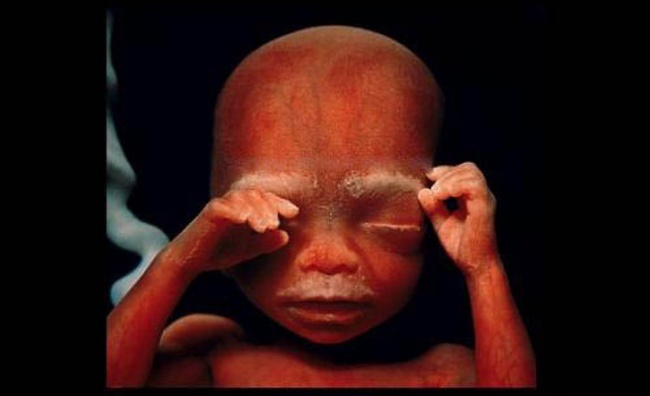

16 Fetus using its hands to explore its own body and surroundings

17 The skeleton, mainly consisting of flexible cartilage and a network of blood vessels, is visible through the skin

18 After 18 weeks

19 19 weeks

20 The fetus is now 20 centimeters long and hair starts growing